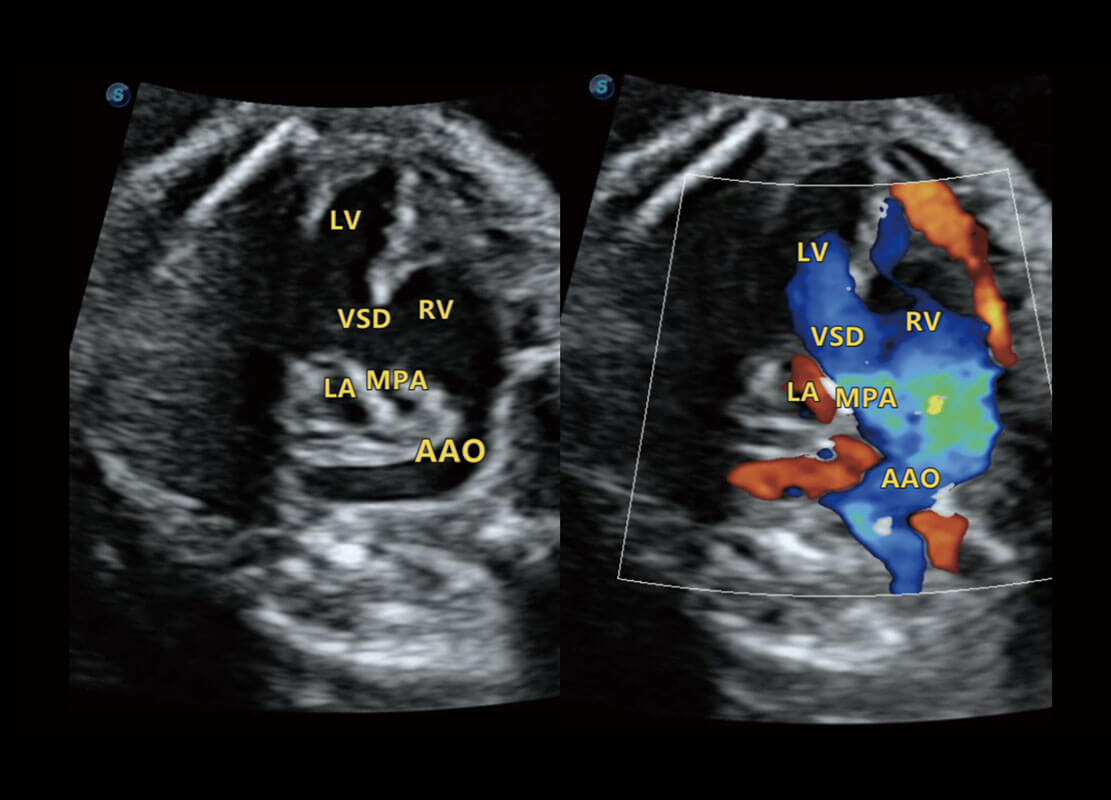

P60搭載一系列胎兒心臟成像技術(shù),實(shí)現(xiàn)精細(xì)的胎兒心臟評(píng)估。

四腔切面

四腔心血流

右室雙出口

胎心容積成像